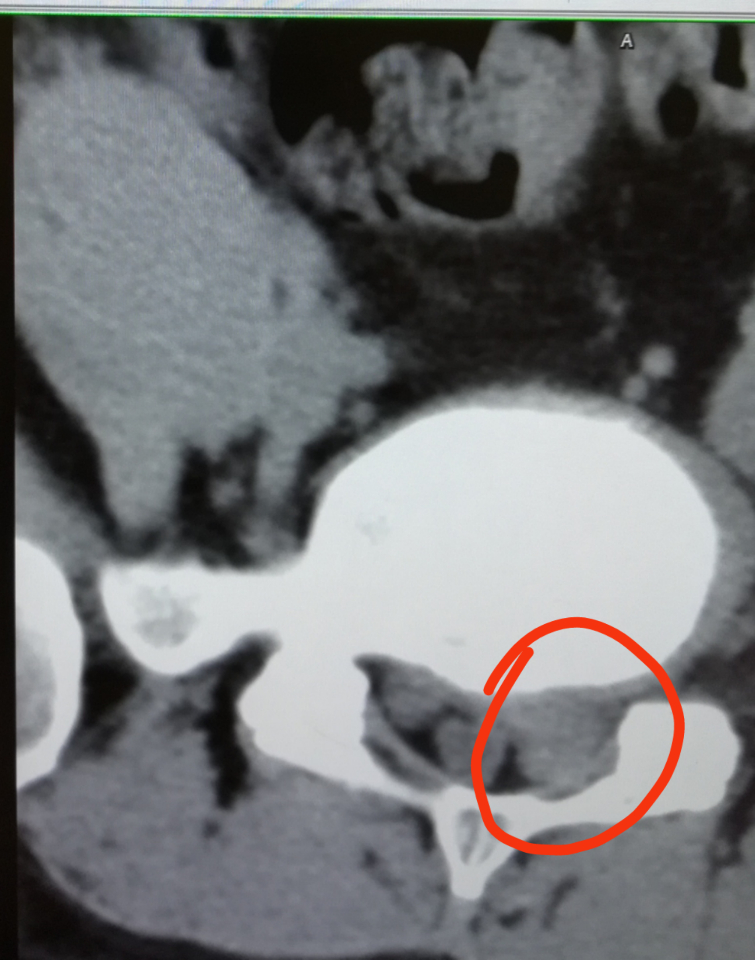

你的椎管严重狭窄了!你的下肢还能走路吗?不过,我可以包治恢复到正常健康人一样。

楼主你这神经根压的都看不到了,还有这个吧卖假药行假医的骗子太多了,你要想认真治疗就多跑几个医院多找几个大夫看一下,你能说一个大夫是骗你的,那么多大夫还能一起串通好了骗你妈